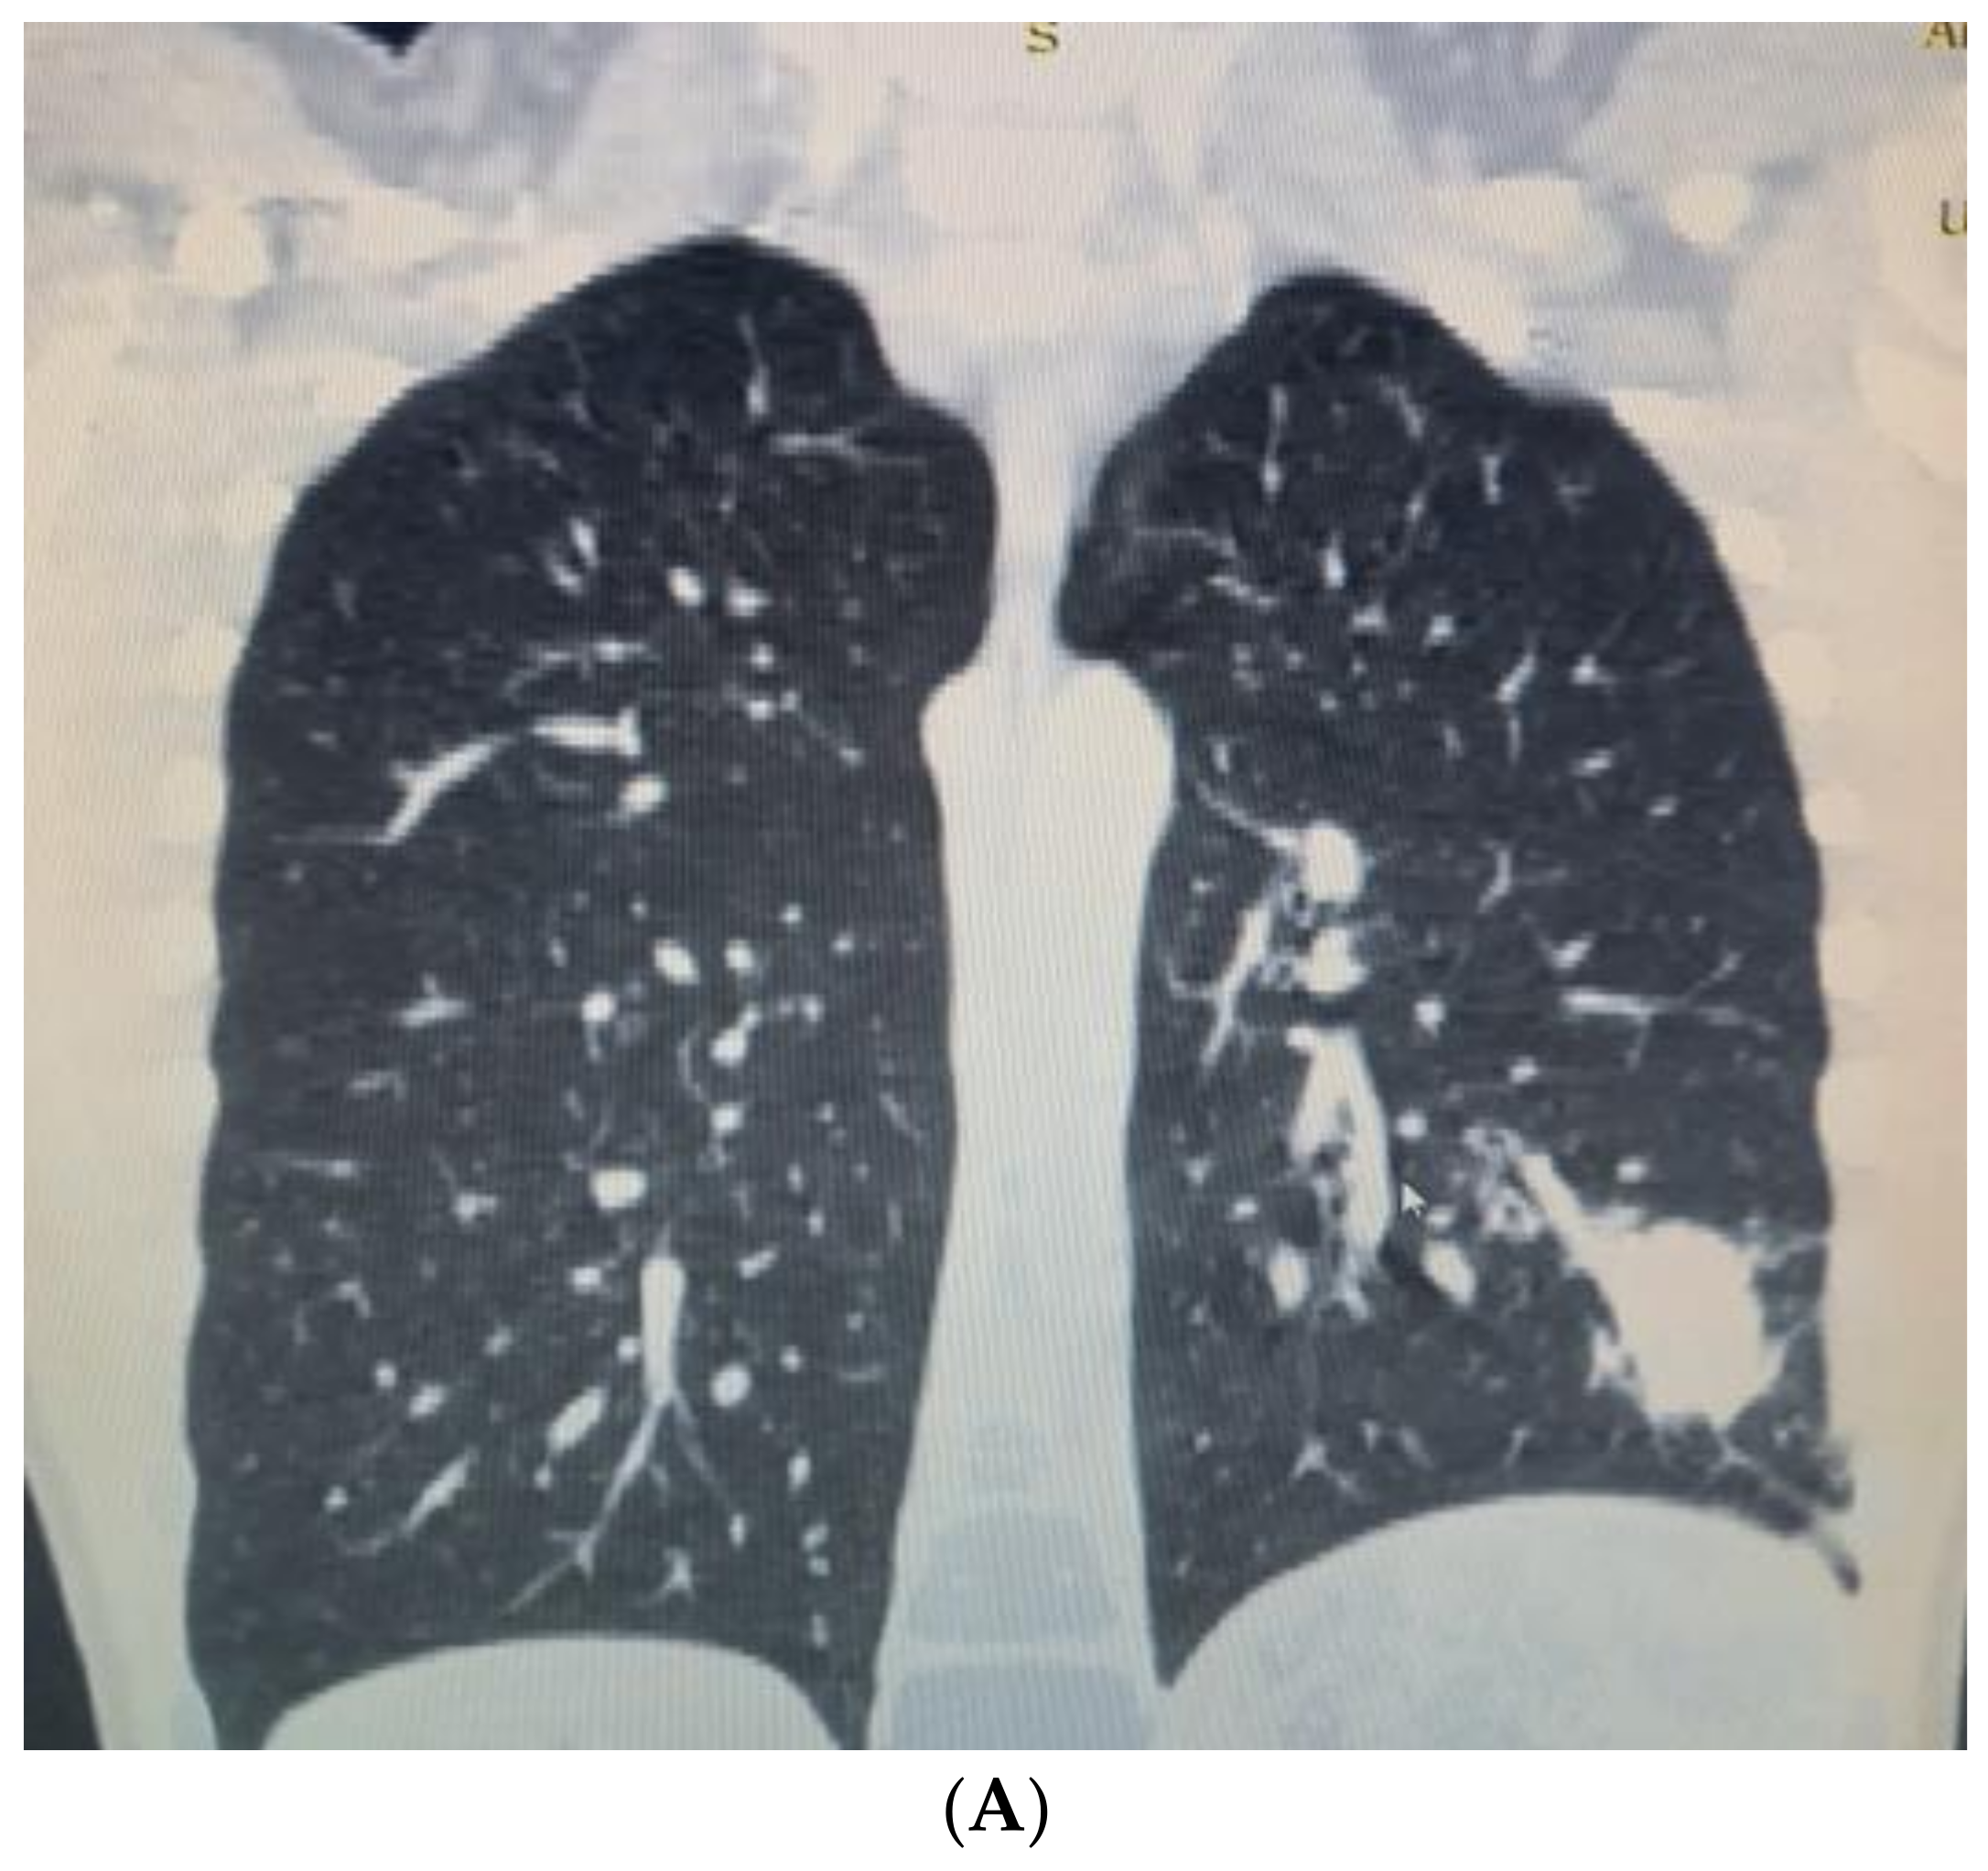

After two weeks, the child was admitted again to the Department of Pediatric Thoracic Surgery. Blood and biochemical tests were in the normal range (leucocytes 8.9 G/L, hemoglobin 136 g/L, hematocrit 0.42 L/L, thrombocytes 281 G/L, CRP 0.06 mg/dL, ASAT 26 U/L, ALAT 17 U/L, creatinine 57 µmol/L). A frontal chest X-ray revealed the persistence of the radiological findings from the last stay (Figure 3). A CT scan showed a zone of consolidation and a typical view of a lung abscess in the left posterior basal segment (Figure 4A,B). Then, the decision for surgery was taken. A left-sided VATS was performed. An abscess (3 cm/4 cm/5 cm) was found in the 10th segment, and an atypical lung resection was performed. After the procedure, the lung specimen was cut, and a foreign body (an awn from the species Hordeum murinum) was found (Figure 5A,B). A 20 Ch drain tube was inserted into the pleural cavity. After the surgery, the improvement was marked. Perioperative and postoperative therapy comprised Sultamicillin, Cefoperazon/Sulbactam, Clindamycin, and postoperative analgesia. The postoperative period was uneventful. The patient was discharged on the 9th postoperative day.

Figure 4. (A). CT scan showing lung abscess in left posterior basal segment—a coronal view. (B). CT scan—an axial view.